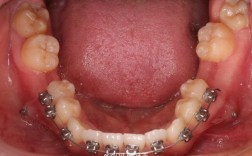

- 数字化舌侧托槽:舌侧矫治因托槽位置隐蔽,对转矩精度要求更高,通过CAD/CAM设计个性化托槽,可实现误差<0.1°的精准控制。